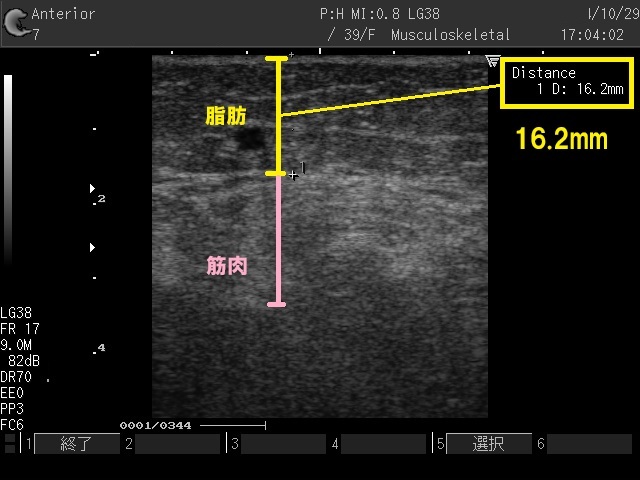

施術前に脂肪の厚みを計測できます

超音波エコーで脂肪の厚みを測ることで、顔の脂肪を減らすべきか、リフトだけにしたほうがいいのか、アドバイスが可能です。

- 顔がコケたくない方は脂肪を減らさないように、皮下3mmでタイトニング

- 顔ヤセ・小顔をしながらリフトアップもしたい方は、皮下7mmで脂肪減少

- 痩身ダイエットでは、脂肪の多い部分に12~13mmに照射し脂肪減少